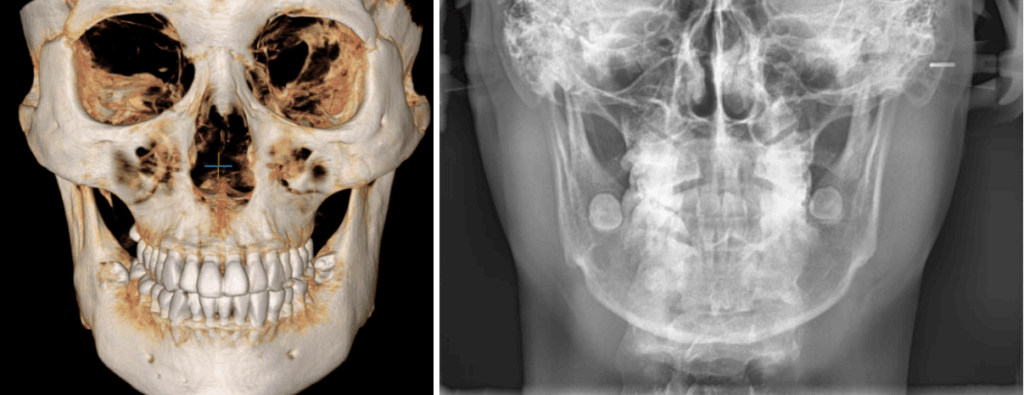

안면 얼굴 분석을 해본 결과,

활짝 웃었을 때 삐뚤빼뚤한 치열이 보이는데요.

위턱 치열과 입술이 오른쪽으로

높게 기울어져 있었습니다.

23.11.24

눈 아래선을 기준으로

골격의 비대칭은 심하지 않았으며,

세팔로 전면 모습에서도

대칭적인 것을 확인할 수 있습니다.

얼굴의 길이가 수직적으로 정상적이고

위아래턱이 조화로운 골격성 1급이었습니다.

더불어 골격에 대한 위아래 앞니의 각도가

알맞은 것을 알 수 있었습니다.

엑스레이를 분석해 보았을 때는

남아 있는 사랑니는 3개로

위턱 왼쪽에만 없었습니다.

위아래 어금니 간 폭경의 비율이

부조화를 보인 것을 볼 수 있습니다.

더불어, 왼쪽 비강의 협착과

상악동 염증 소견이 보입니다.